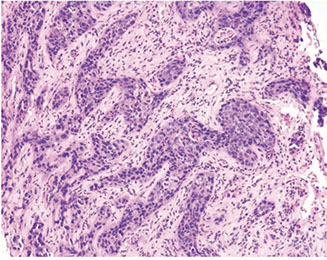

PIN Like (Ductal) Adenocarcinoma

 Unusual (1.3%) PCA variant cytologically and architecturally resembling HGPIN

 Characterized by non cribriform stratified epithelium similar to flat, tufted and/or micropapillary PIN

 Greater degree of glandular crowding and/or

disorder than usually seen in PIN

 Malignant epithelial cells are columnar or cuboidal

 Nuclei are rounded or oval to fusiform

Versus HG-PIN, PIN-like adenocarcinoma:

 Presence of cystically dilated glands

 Greater predominance of flat architecture

 Less frequently prominent nucleoli

 Long strips of PIN like epithelium on the edge of

the core

Absence of basal cells

 Graded as GS6 (GG1)

PIN-like ductal AC

PIN-like ductal adenocarcinoma, CDX2-, PSA+, p63-